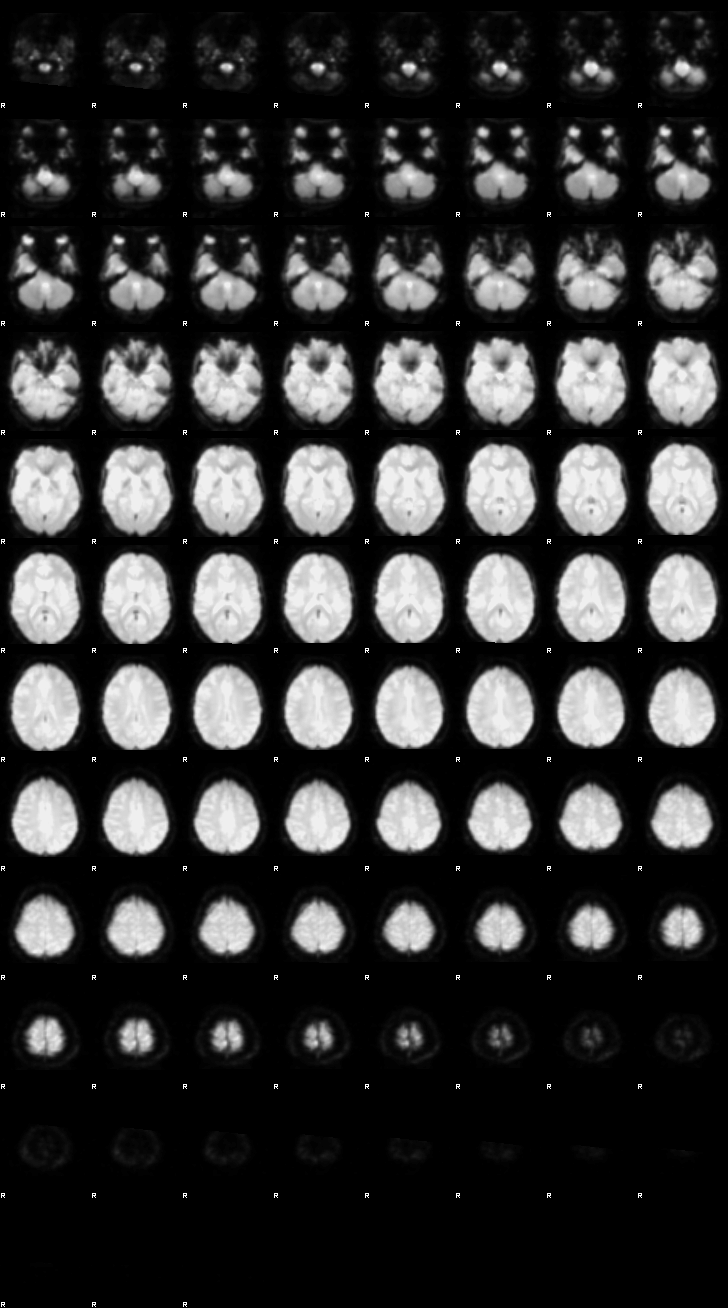

Visualization of First-level Design and Results (Run 1)#

Below, the design matrix and selected results from the first run are shown. Since both runs use the same design and contrasts, the results of the second run can be explored using the same approach.

Let’s now display the thresholded activation maps. A voxelwise threshold of Z > 3.1 was applied, followed by cluster-level correction at p < 0.05 (corrected for multiple comparisons).

zstat3 - C3 (incongruent-congruent)

display(Markdown("#### Incongruent-Congruent"), rendered_thresh_zstats3)

Incongruent-Congruent